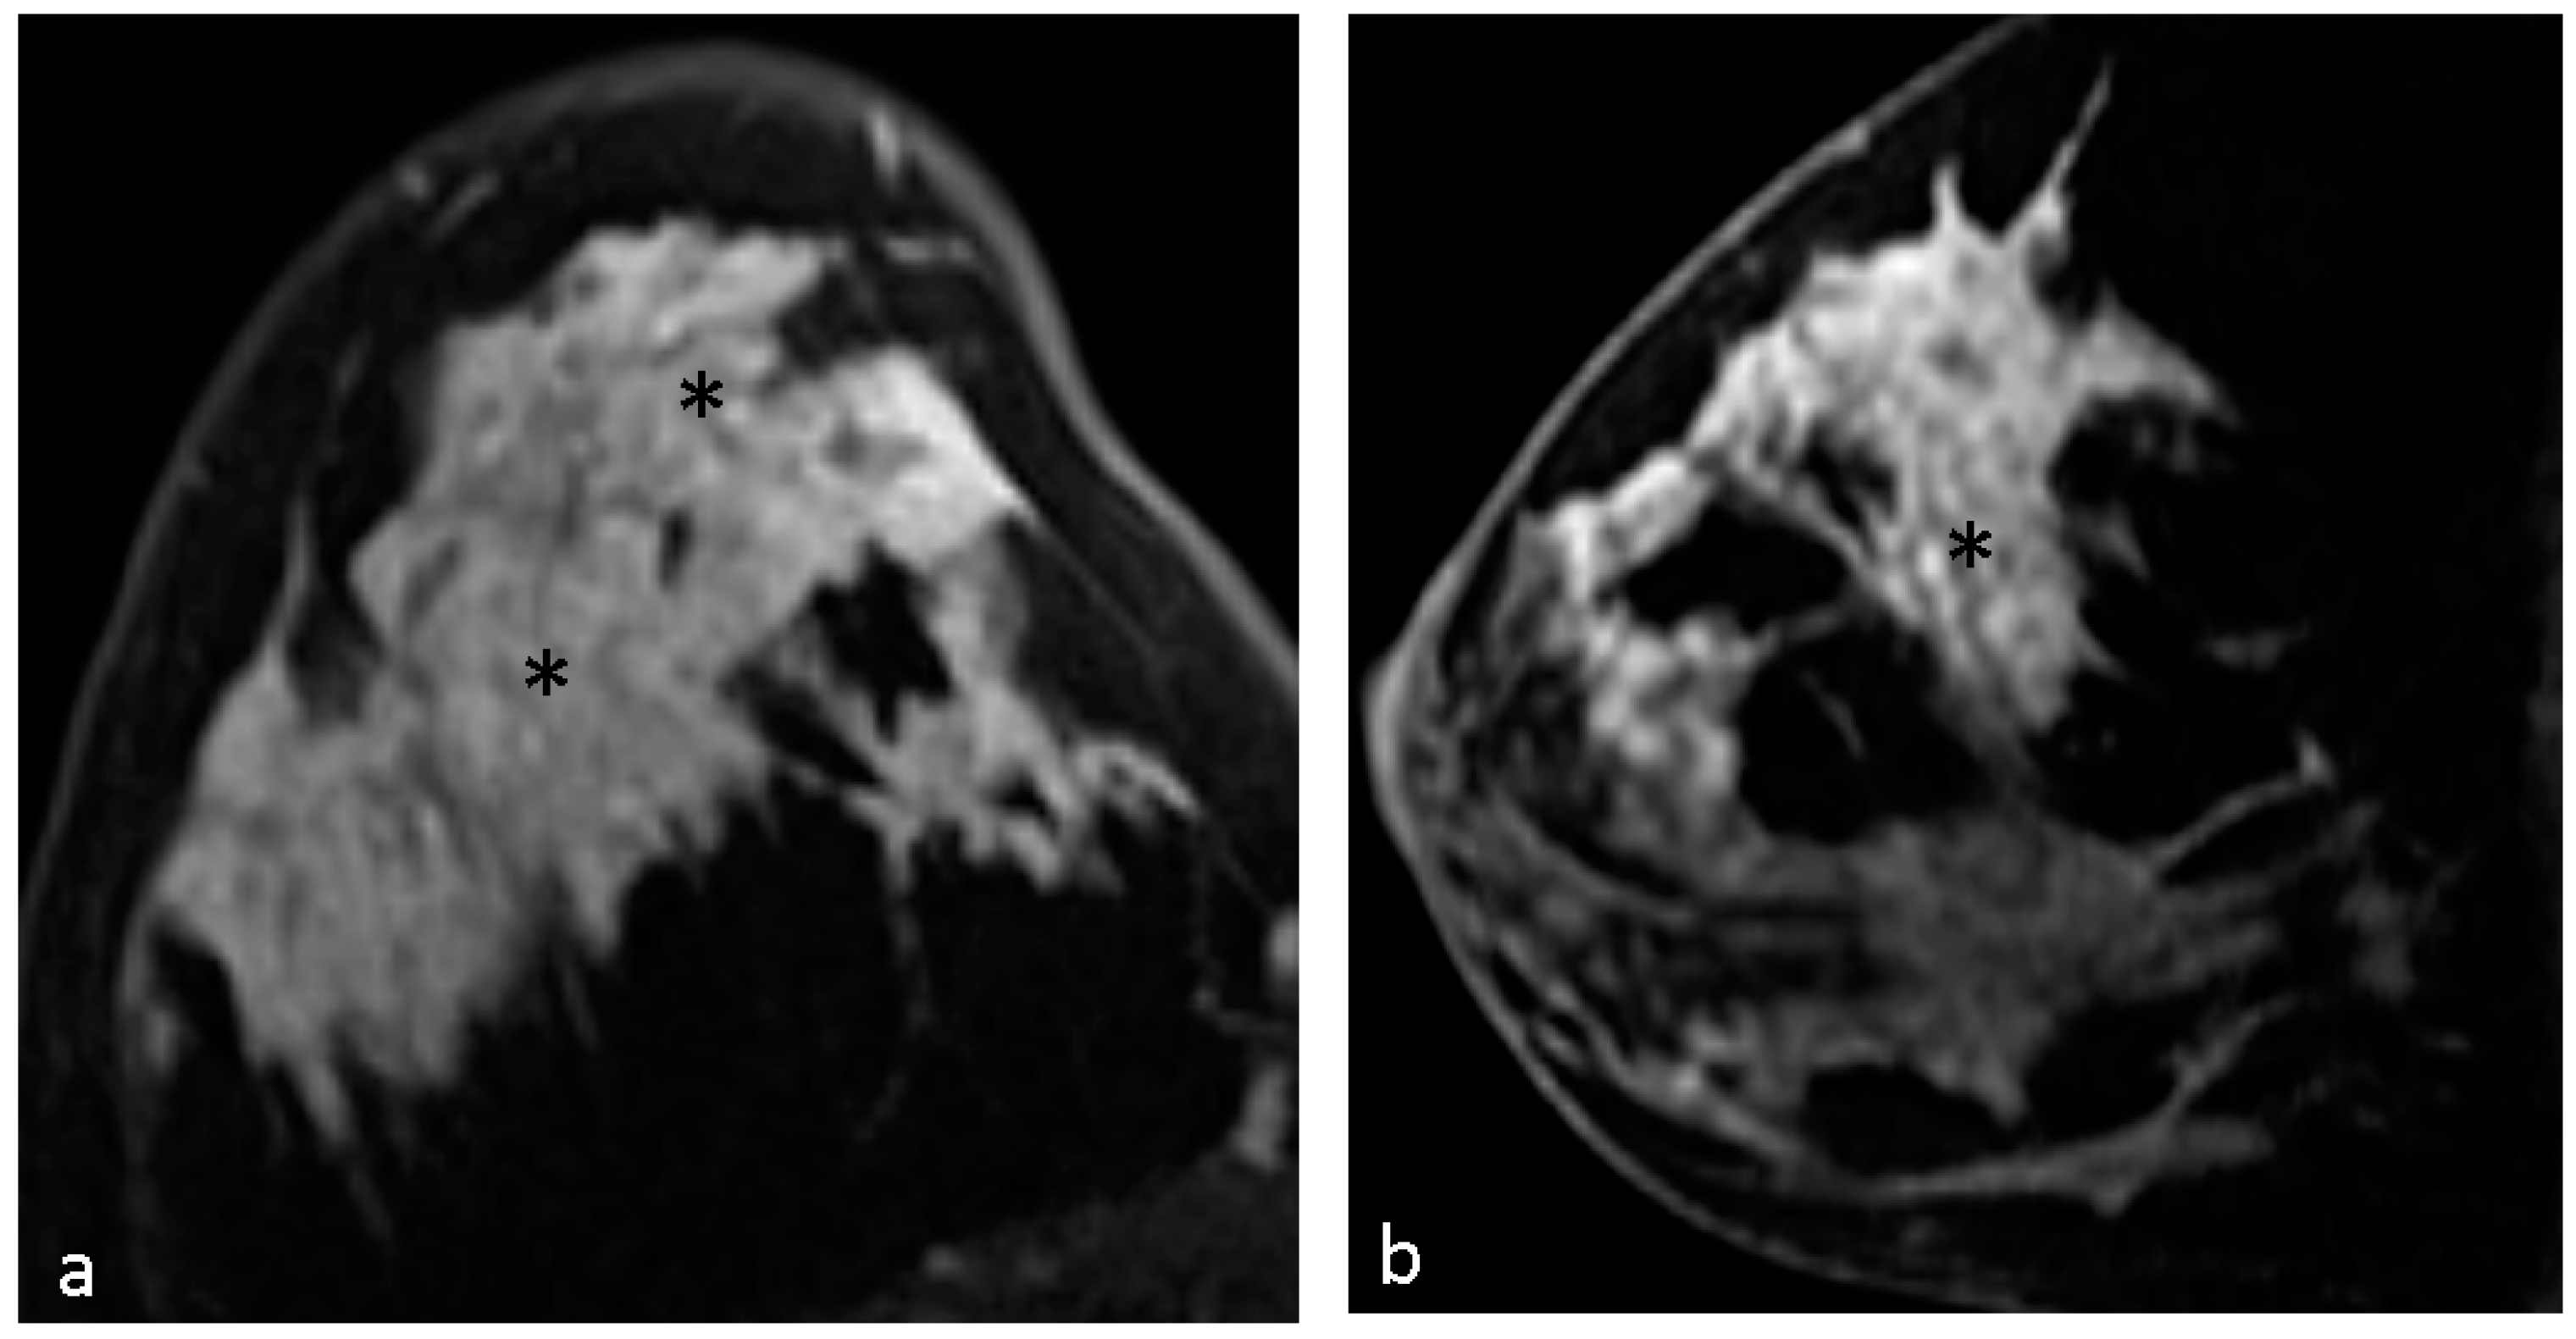

| Clustered ring enhancement | 31 (53.4%) |

| Clump enhancement | 17 (29.3%) |

| Heterogeneous enhancement | 8 (13.8%) |